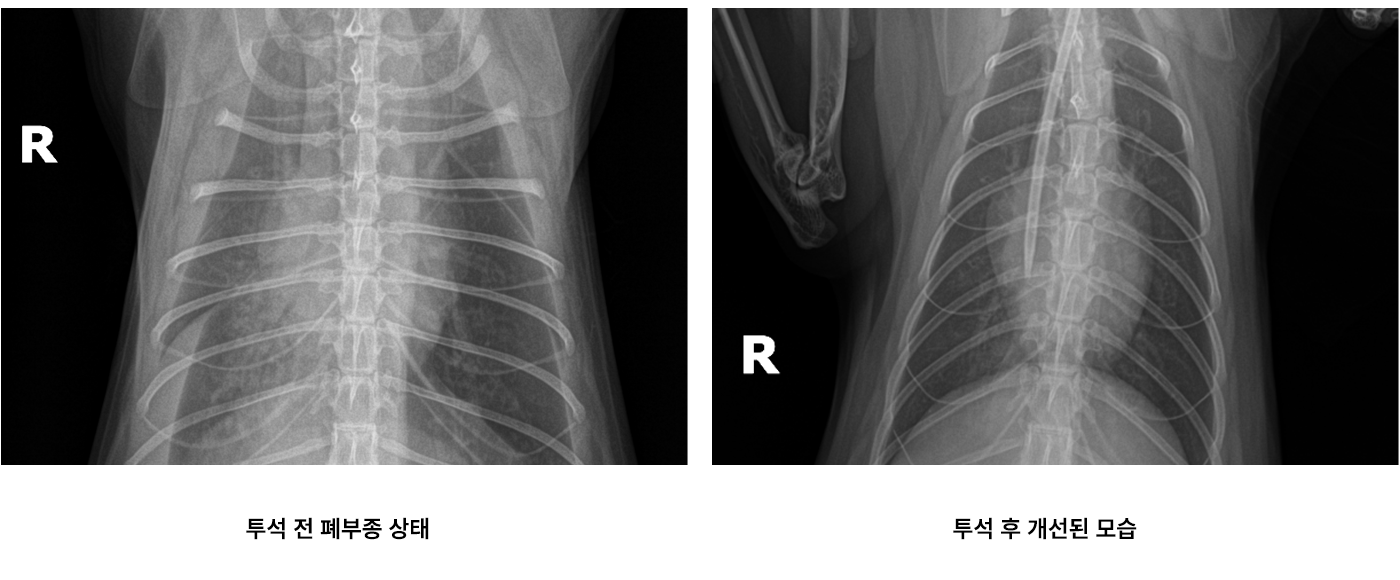

투석 치료 실제 사례

선천적으로 1개의 신장만 가지고 태어난 환자가 급성 신부전으로 내원하여 CRRT 투석을 진행한 사례입니다. 심각한 상태였음에도 1차 투석만으로 핍뇨 증상 완화 및 신장 기능 회복, 폐부종 개선 후 퇴원하였습니다